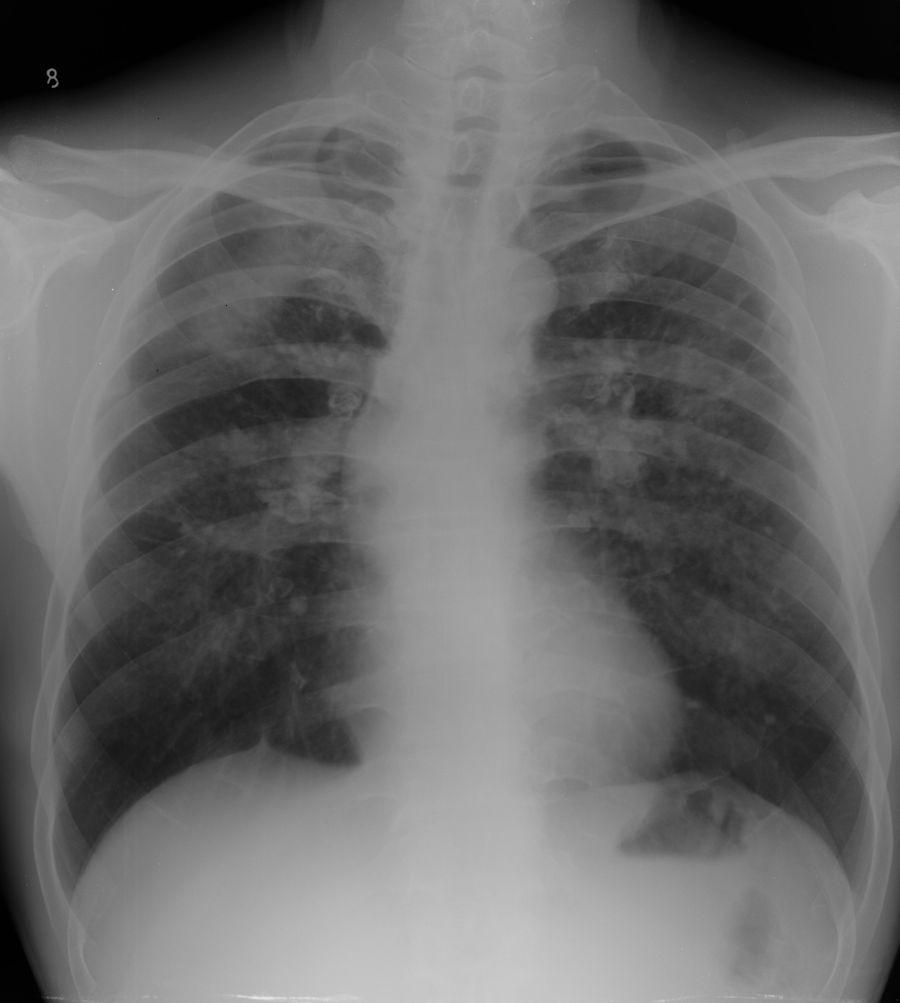

标题: X4980:男,55岁,咳嗽半年余,30余年打石史,20年前发现钙化 [打印本页]

男,55岁,咳嗽半年余,30余年打石史,20年前发现钙化

符合iii期矽肺。

结合病史,考虑矽肺iii期

四、三期矽肺(代号ⅲ)

(一)ⅲ 有大阴影出现,其长径不小于2cm,宽径不小于1cm。

(二)ⅲ+单个大阴影面积或多个大阴影面积的总和超过右上肺区面积者。

矽结节和矽结节融合符合三期矽肺。